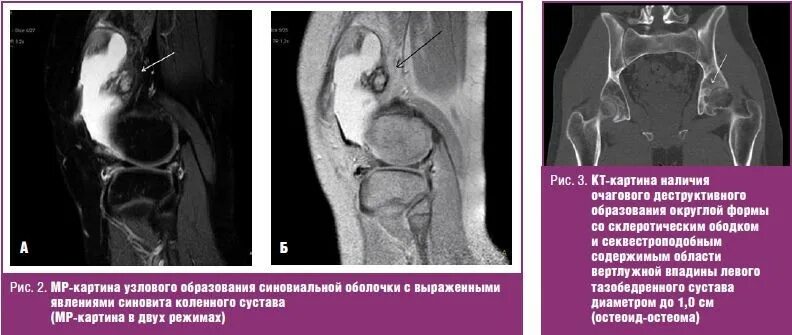

Мрт при боли в суставах